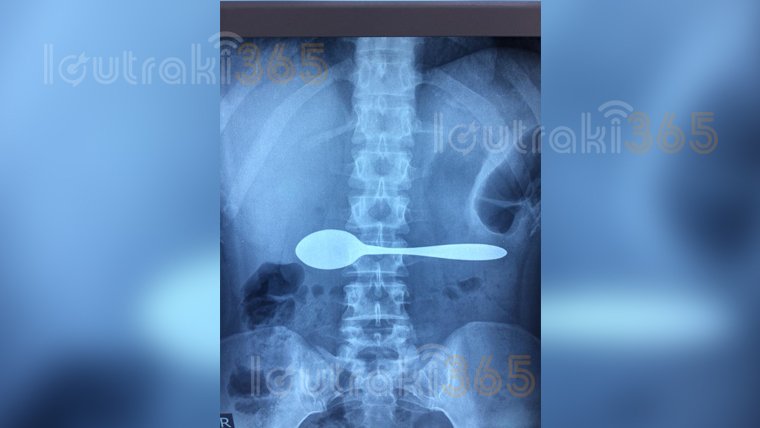

Δεν πίστευαν στα μάτια τους οι γιατροί του νοσοκομείου στην Κόρινθο, όταν είδαν την ακτινογραφία 35χρονη ασθενούς.

Κι αυτό γιατί η ίδια μόλις έφτασε εκεί τους είχε πει πως είχε καταπιεί ένα κουτάλι, πράγμα που επιβεβαιώθηκε και από τις εξετάσεις.

Μόλις οι γιατροί διαπίστωσαν πως το κουτάλι βρίσκεται στο στομάχι της, έστειλαν αμέσως την γυναίκα στο εφημερεύον νοσοκομείο της Αθήνας, καθώς έπρεπε να εξετασθεί από γαστρεντερολόγο που δεν υπήρχε στο νοσοκομείο Κορίνθου.

Σύμφωνα με πληροφορίες πάντως, η ζωής της 35χρονης δενδιατρέχει πλέον κίνδυνο.